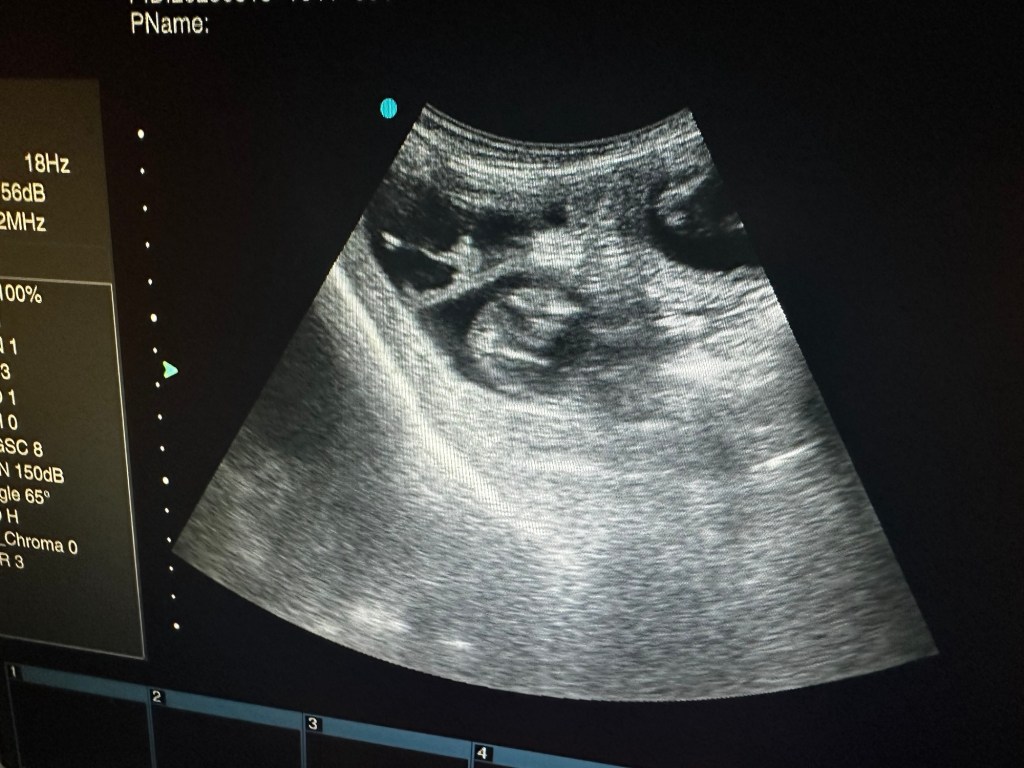

I dag har vi tatt ultralyd og begge tispene våre er drektige. Oliane med et lite kull og Naya med et stort kull. Elevene var med på ultralyd og nå er det bare å vente frem til røntgen uken før forventet termin.